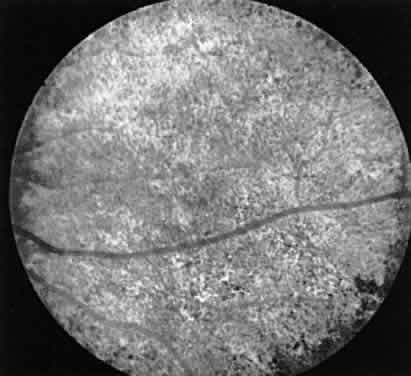

large percentage of such cases the female carrier shows fundus changes

in the absence of any subjective complaints.12 These may consist of an unusual scintillating reflex in the macular area

or a clumping of pigment in the periphery (Fig. 13). However, these changes are not always seen. In such cases electrophysiologic

studies provide the answer, for it has been found that certain

electrophysiologic abnormalities also are seen in the majority of female

carriers, even those with no fundus abnormalities. These consist

of a prolonged photopic b-wave implicit time and/or a reduction in the

amplitude of the scotopic b-wave in a fully dark-adapted eye.13  Fig. 13. Female carrier of X-linked retinitis pigmentosa. Fundus photographs of

a 48-year-old female with vision of 20/20 OD and OS. Left. Macular area shows an unusual scintillating reflex around the entire parafoveal

region. Right. Retinal periphery showing an isolated area of retinal pigment epithelial

loss with associated clumps of pigment. Fig. 13. Female carrier of X-linked retinitis pigmentosa. Fundus photographs of

a 48-year-old female with vision of 20/20 OD and OS. Left. Macular area shows an unusual scintillating reflex around the entire parafoveal

region. Right. Retinal periphery showing an isolated area of retinal pigment epithelial

loss with associated clumps of pigment.